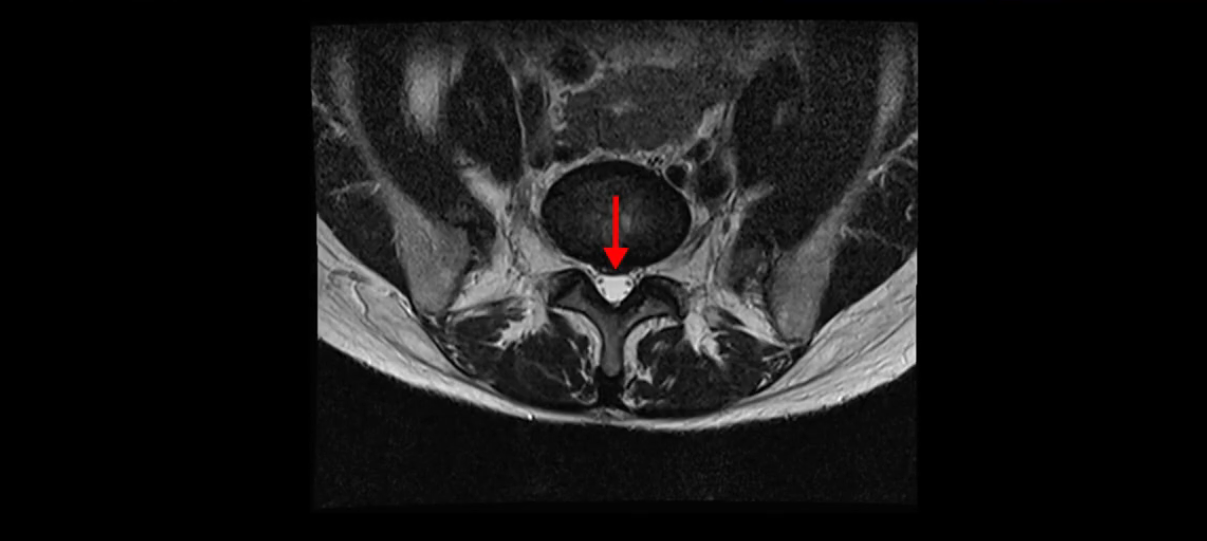

이분 MRI를 보시면 두 마디의 퇴행성디스크가 있습니다. 그리고 디스크가 조금씩 밀려 나와 있고요. 그런데 디스크 탈출 정도는 두 마디 다 심하지 않습니다. 4번 5번에는 디스크 탈출이 약간 있고,

또한 양쪽 신경 가지가 빠져나가는 추간공은 매우 넓은 상태입니다.

중요한 것은 이 정도 경미한 탈출과 협착으로는 양쪽 다리가 저리고 아플 수가 없습니다.

이분 MRI를 보시면 퇴행성디스크가 있고 약간의 협착이 있지만 이 정도의 퇴행성디스크와 협착으로는 신경이 눌려서 양쪽 다리가 저리고 아픈 증상이 나올 수가 없습니다. 그래서 MRI와 이 환자분의 다리 증상이 매치가 안 된다고 하는 의사들이 많은 겁니다.